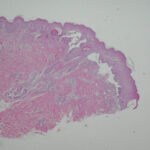

Histopathology. The bullous pemphigoid-like presentation described above is the most common form of EBA. The subepidermal blisters are inflammatory. The predominant infiltrating cells are lymphocytes and neutrophils in perivascular and focal interstitial array. Eosinophils are present in variable numbers . In the classic form, the subepidermal blisters are noninflammatory ; fibrosis and milia formation are often present. |